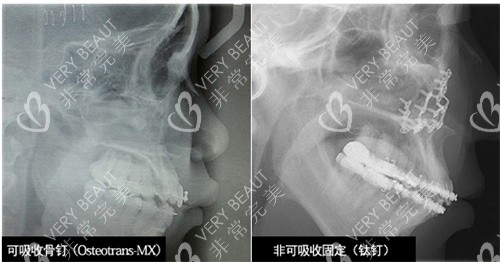

就說(shuō)韓國(guó)必嫵雙鄂手術(shù)他能做到第4代,并且該院使用可吸收的骨釘固定在CT片上不露餡。

特色二:韓國(guó)必嫵隱形雙鄂采用可吸收骨釘

另外對(duì)于一些患者非常不愿意在自己的骨頭上打鈦釘,院方自己也有專屬的可吸收骨釘來(lái)進(jìn)行替代。這樣在拍CT的時(shí)候,是不會(huì)看出頜面有打過(guò)鈦釘?shù)姆浅_m合演藝圈的人士以及對(duì)自己要求比較高的朋友。